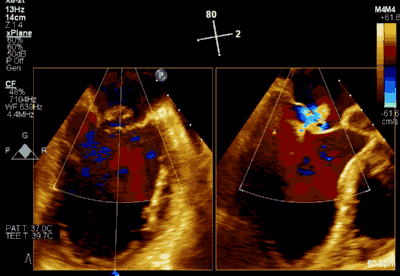

患者为66岁老年男性,4个月余前因“急性心肌梗死合并二尖瓣后叶腱索断裂”出现心源性休克,在IABP支持下仍反复发作左心心力衰竭,经过急诊血运重建联合优化药物治疗后症状好转,但术后多次发作严重左心心力衰竭,超声心动图评估二尖瓣反流急性增加至极重度,左房、左室显著扩大。此次主诉“反复胸闷、气促4月余”入院。诊断:心脏瓣膜病 二尖瓣脱垂伴重度关闭不全 二尖瓣后叶腱索断裂 心功能IV级(NYHA分级) 。术前经胸超声心动图示:全心扩大,二尖瓣后叶脱垂、腱索断裂合并重度关闭不全(DMR 4+)。心脏测值:LA 45mm LVD 55mm EF% 61% PASP 82mmHg。经食管超声心动图示:二尖瓣环左右径33mm,反流束缩流颈宽度为5.5mm,EROA 0.67cm2(PISA),舒张期二尖瓣口平均跨瓣压差5mmHg。

▲ 术前超声检查显示重度二尖瓣反流